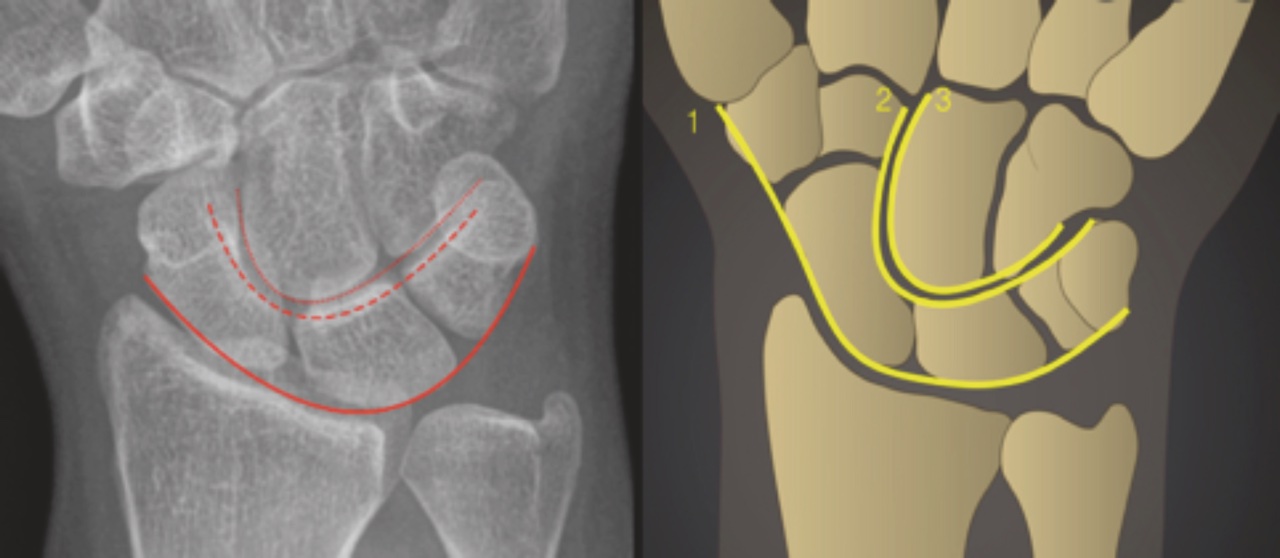

La diagnosi è confermata tramite radiografia in proiezioni ortogonali (antero-posteriore e laterale), in cui si evidenziano l’interruzione degli archi di Gilula (Figura 2), lo spostamento del capitato e l’orizzontalizzazione dello scafoide (segno della “tazza rovesciata”).

In caso di lussazione perilunare dorsale, il semilunare assume, in proiezione PA, una forma triangolare con apice distale, espressione della rotazione dell’osso in flessione che proietta distalmente il suo corno dorsale di forma triangolare (segno del “pezzo di torta”). Può essere infine evidente una diastasi scafo-lunata, evenienza che va sospettata in tutti i casi in cui la distanza tra scafoide e semilunare risulti maggiore di 2 mm rispetto al controlaterale (segno di Terry Thomas) o se è presente il segno dell’anello di Bell, determinato dalla flessione e parziale rotazione dello scafoide che avviene in caso di rottura del legamento scafo-lunato (polo prossimale e tubercolo si sovrappongono dando luogo a questo caratteristico segno che non è normalmente presente se l’osso è sul suo asse normale). (15)(16)